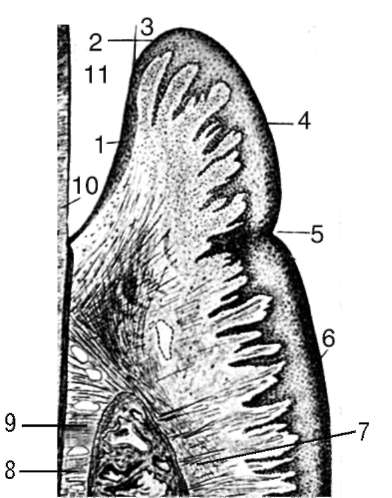

Рис. 4-2. Схема строения десны (Гемонов В.В.): 1 - эпителиальное прикрепление; 2 - дно десневого кармана; 3 - кутикула эмали; 4 - свободная десна; 5 - десневой желобок; 6 - прикрепленная десна; 7 - вершина альвеолярного отростка; 8 - перицемент; 9 - цемент; 10 - дентин коронки; 11 - пространство, до декальцинации занятое эмалью